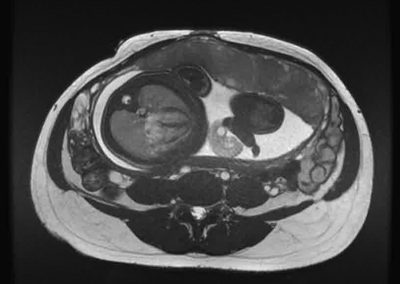

L’Université Paris Cité franchit une nouvelle étape dans le domaine de l’imagerie médicale anténatale avec l’acquisition d’un système d’Imagerie par Résonance Magnétique (IRM) 1,5T ARTIST™ de GE HealthCare. Cet équipement de pointe renforce les capacités de la Plateforme LUMIERE à l’hôpital Necker-Enfants malades, plateforme intégrée de soins, de recherche clinique et d’enseignement en imagerie médicale de la femme enceinte, du fœtus et du placenta.

L’acquisition de cette nouvelle IRM s’inscrit dans le cadre du protocole de recherche « LUMIERE SUR LE FETUS », dont les objectifs sont d’améliorer la prise en charge des pathologies anténatales, d’affiner leur pronostic et de contribuer à la réduction de la morbidité et de la mortalité à court, moyen et long terme. Cette acquisition a été rendue possible grâce au don exceptionnel de la Fondation LUMIERE d’un montant de 250k euros ainsi qu’au soutien de l’Université Paris Cité à hauteur de 670k euros.

Depuis 2020, la Plateforme LUMIERE offre aux femmes enceintes volontaires, entre 16 et 36 semaines d’aménorrhée et suivies à l’hôpital Necker-Enfants malades, la possibilité de participer activement à l’avancée de la recherche en médecine fœtale, tout en bénéficiant d’une IRM fœtale au cours de leur grossesse, réalisée dans un cadre sécurisé et encadré.

L’inclusion de ces patientes, depuis leur accueil jusqu’à la réalisation des examens d’imagerie, puis l’analyse des images et l’interprétation des résultats par des équipes expertes, enrichit une base de données structurée, unique au monde, au service de la recherche et de l’innovation en imagerie anténatale et en médecine fœtale.